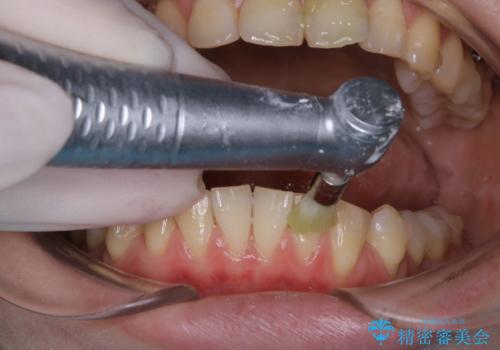

インビザライン矯正治療中のPMTC

- インビザライン矯正中に茶色が気になるとのことで来院されました。PMTC30分コースを行いました。

インビザラインでの治療中の患者様のクリーニング前後写真です。